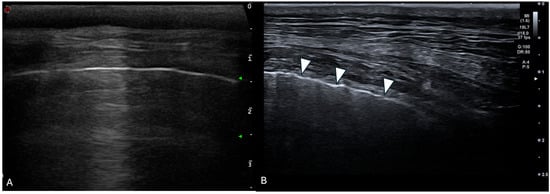

Cover Story (view full-size image): Lumbosacral radiculopathy is a frequent cause of back pain in dogs and humans, often associated with intervertebral disc herniation or foraminal stenosis. In medicine, transforaminal epidural injections are widely used to deliver therapeutic agents near affected spinal nerves. This study evaluated an ultrasound- and fluoroscopy-guided technique for lumbosacral foraminal injections in canine cadavers, assessing injectate distribution through fluoroscopy, computed tomography, and anatomical dissections to determine its precision and potential clinical application. View this paper